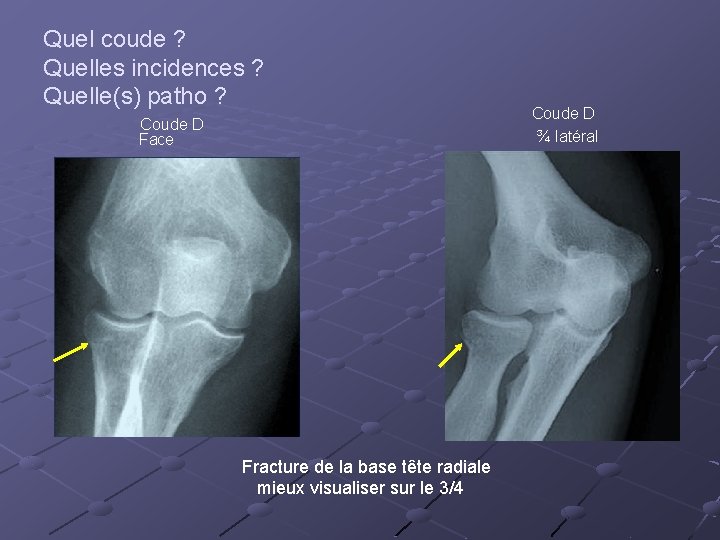

Quel coude ? Quelles incidences ? Quelle(s) patho ? Coude D Face Fracture de la base tête radiale mieux visualiser sur le 3/4 Coude D ¾ latéral